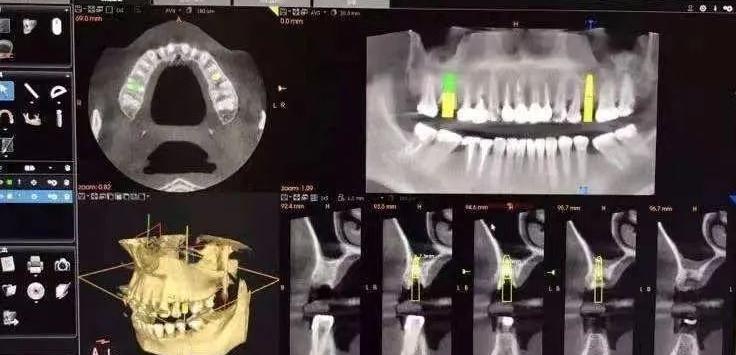

其基本原理是X线发生器以较低的射线量(通常球管电流在10毫安左右)围绕投照体做环形数字式投照,然后将围绕投照体多次数字投照后“交集”中所获得的数据在计算机中“重组”,进而获得高清三维图像。卡瓦X-TREND“三合一”CBCT即具有口腔曲面断层片、头颅侧位定位片和多功能CT三种拍摄功能,满足了口腔临床诊断的所有需要。

5、口腔种植方面:涵盖种植牙的每一个种植细节,提供可靠理论依据,确保种植牙手术的成功率。